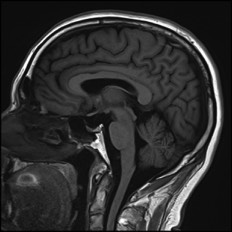

NEUROSURGERY

Surgery of the brain, spine and peripheral nerves